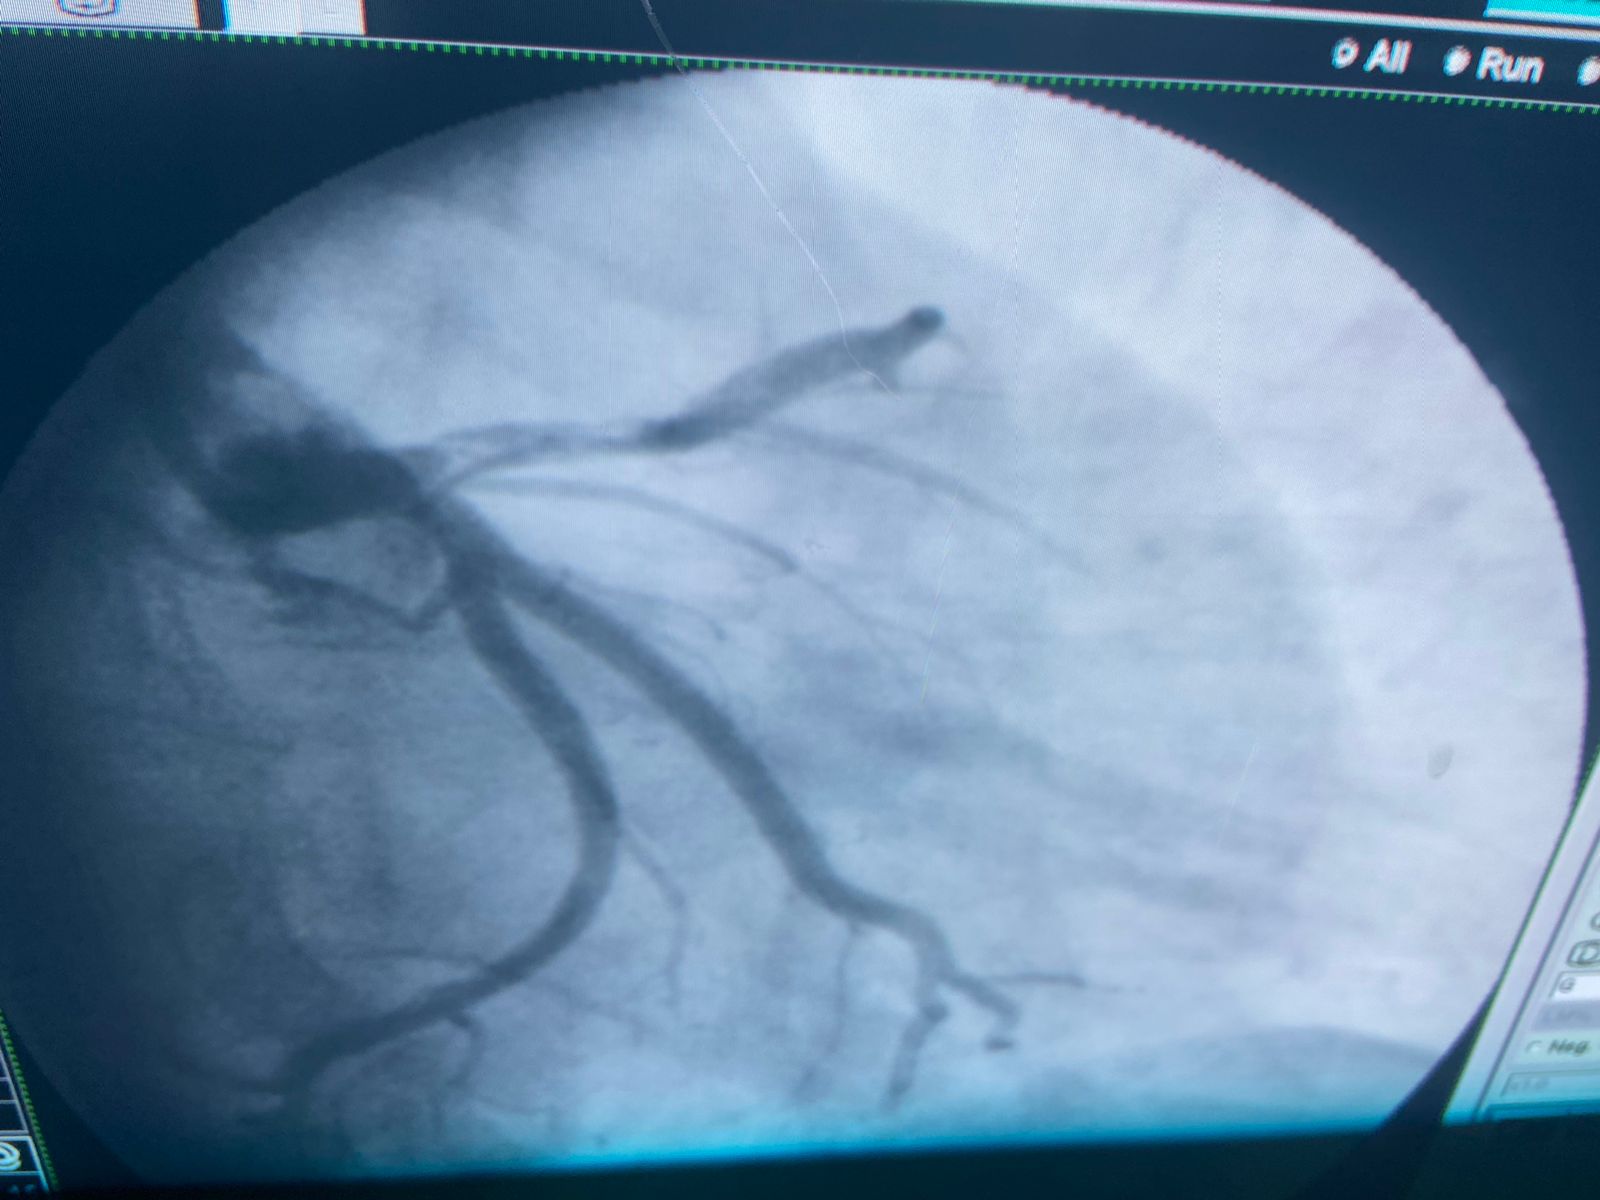

أعلن الدكتور مصطفى عبد الخالق، رئيس جامعة سوهاج، نجاح فريق طبي بوحدة قسطرة القلب وقسم جراحة الأوعية الدموية، في التدخل العاجل لإنقاذ ساق مريض من البتر، يبلغ من العمر 24 عامًا، وذلك باستخدام دمج بين التدخل الجراحي والقسطرة التداخلية، وهي تعد من التدخلات التي تحتاج إلى مهارة وتجهيزات خاصة.

من جانبه أفاد الدكتور شرف الدين شاذلي، رئيس وحدة قسطرة القلب بالمستشفى الجامعي، بأن فريق العمل بجراحة الأوعية الدموية، قام بعمل سحب وإذابة جلطة الساق، وبعدها تدخل أطباء وحدة القسطرة لعمل قسطرة عاجلة للقلب لسحب الجلطة وتركيب دعامة الشريان التاجي عن طريق الذراع، وبفضل الله وعنايته، المريض الآن بحالة جيدة، ويتماثل حاليًا للشفاء في عناية القلب بالمستشفى الجامعي.